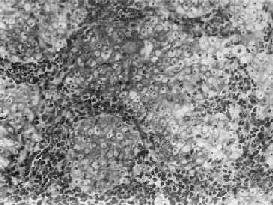

图9-6 鼻咽泡状核细胞癌

癌细胞境界不清,呈合体状,核大圆形,染色质少,呈空泡状,含1~2个肥大的核仁,癌细胞间有淋巴细胞浸润